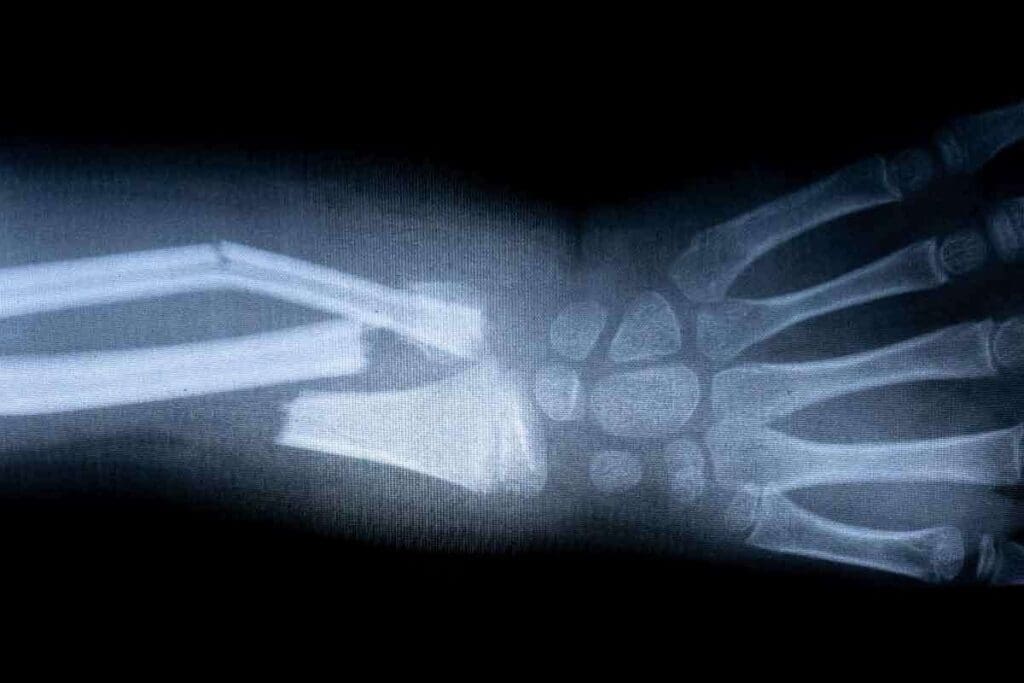

X-ray imaging uses special radiation to show bones and other body parts. When an X-ray beam hits the body, different parts absorb it differently. Bones, being denser, absorb more and look white on the image. Softer tissues show up in gray or black.

This method is great for spotting bone fractures. A break in the bone looks like a dark line or gap.

Anatomical Challenges and Overlapping Structures

Complex areas like the spine, pelvis, and wrist are hard to image with X-rays. This is because many bones overlap, making it hard to see fractures clearly. A radiologist notes that X-rays might miss fractures in these areas because of bone overlap.

X-rays work differently on different bones. For example, finding stress fractures or small cracks in bones like the scaphoid or femoral neck is tough with X-rays alone. In these cases, we use MRI for a more precise diagnosis.